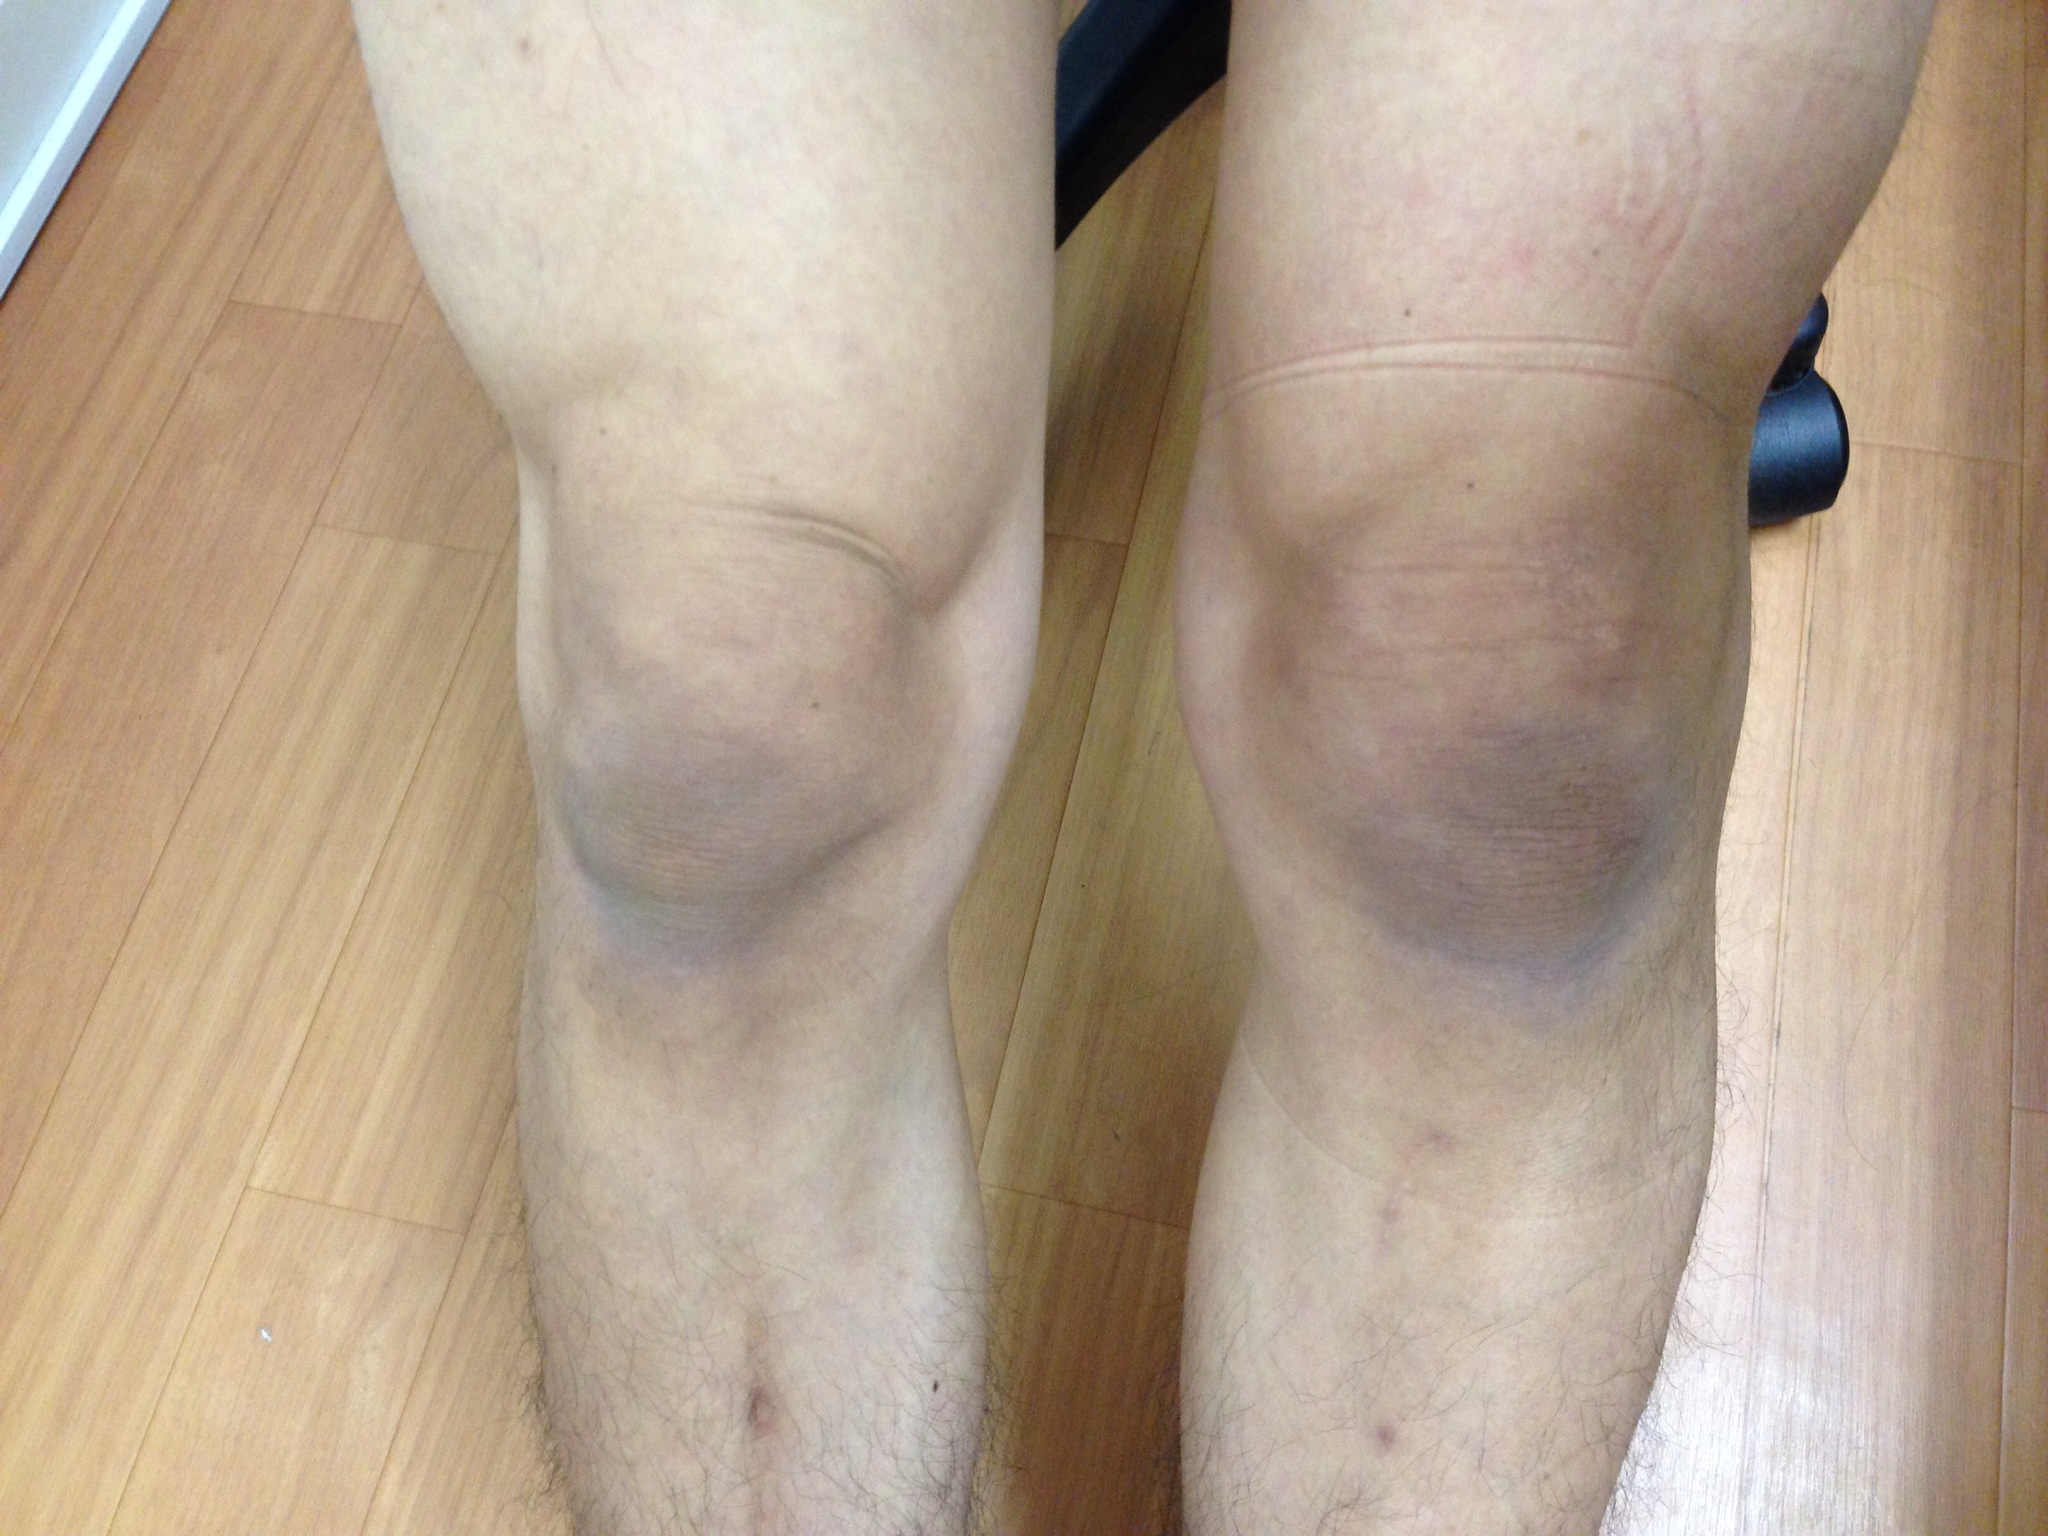

肺水腫が慢性的な場合、体のシステムが補償できなくなるまでは、通常、症状はそれほど重くなりません。症状には次のようなものがあります。